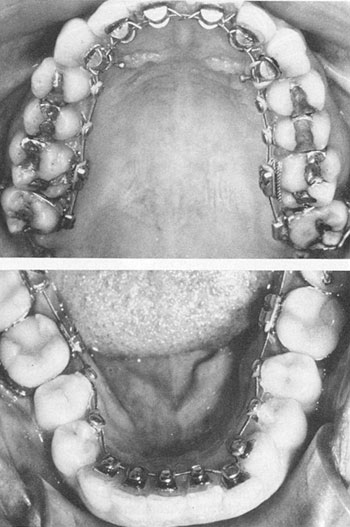

During 1979 and 1980, a number of modifications were made. With difficulties in maintaining control of the posterior segments and the encroachment of the second molar tube on tongue space, it was decided to produce a terminal tube for the first molars and to treat the posterior segments with conventional buccal segmental mechanics. Lingual brackets were placed on bi-cuspids when possible, and the lingual archwire was terminated at the first molars.

Once the transition was made from a continuous lingual arch to a combined lingual and buccal segmental approach, a number of options developed. For example, lower bicuspids, which frequently present extremely short lingual crown length, could be bypassed on the lingual in favor of a buccal segment, bicuspids through molars. This presents no great esthetic compromise on most patients (Fig. 5).

Fig. 5 Phase IV Appliance, lingual and buccal approach.

Fig. 6 Phase III Appliance (above) with flat bite wing on cuspid. Phase IV Appliance (below) with tapered cuspid bite plane.